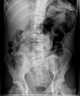

Pneumomediastinum with retroperitoneal extension

Abnormal left upper quadrant abdominal gas collection

Abnormal right upper quadrant abdominal gas collection